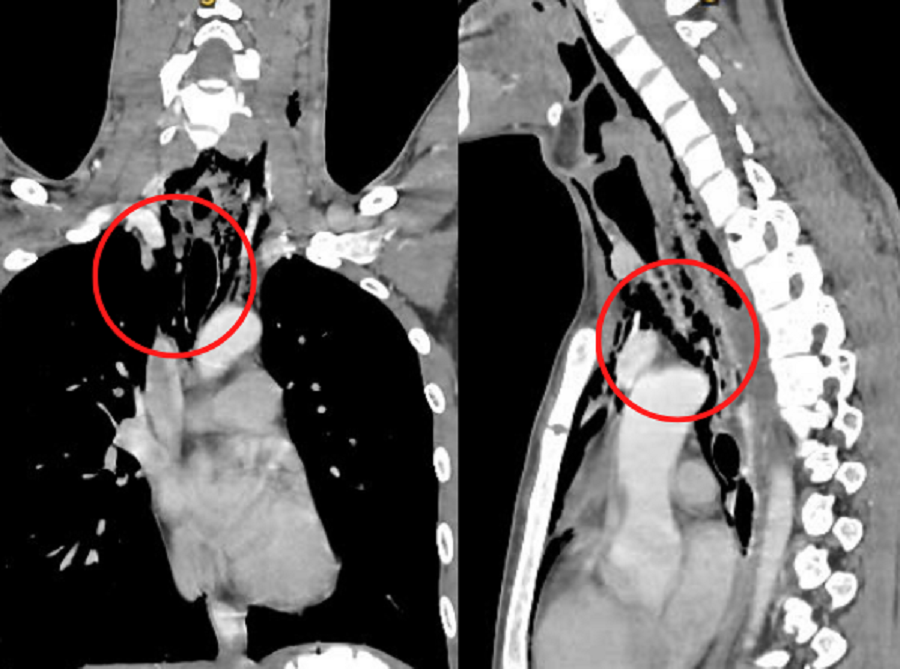

| Hình ảnh kiểm tra cho thấy vị trí thực quản bị lưỡi kiếm đâm thủng (khu vực khoanh tròn) |

Ngay sau đó T. rút kiếm ra khỏi miệng và nhanh chóng đến bệnh viện cấp cứu. Qua nội soi, các bác sĩ ghi nhận, bệnh nhân bị rách thực quản khoảng 7mm (đoạn 1/3 trên). Hình ảnh kiểm tra lồng ngực cho thấy, người bệnh bị tràn khí trung thất và mô mềm vùng cổ.